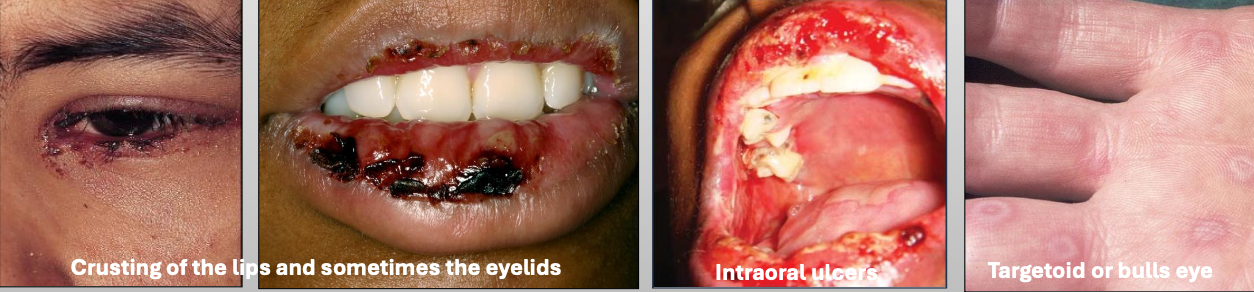

What is Erythema Multiforme (EM)

A blistering ulcerative mucocutaneous condition of uncertain pathogenesis. You see a spectrum of hypersensitivity reaction. The sisease lasts 2-6 weeks (self limiting); 20% have recurrent episodes

What is the cause of Erythema Multiforme (EM)?

Herpes virus (HSV)

Mycoplasma pneumoniae

Medications

What are the clinical features of Erythema Multiforme (EM)

You get prodromal signs a week before

Crusting of the lips and sometimes the eyelids

Intraoral ulcers

Targetoid or bulls eye

What demographic does Erythema Multiforme (EM) affect?

Young M>F

What is the treatment for Erythema Multiforme (EM)?

Steroids

IV rehydration

Topical anesthetic

Discontinue drug

What are characteristics of minor Erythema Multiforme (EM)?

Mild

Young, Male > female

Starts on skin of extremities, oral lesions appear

Crusting on lips

Usually due to herpes (HSV)

What are characteristics of major Erythema Multiforme (EM)?

Wide spread skin lesions + 2 or more mucosal sites

(Oral + ocular or genital)

Ocular scarring may occur in severe cases (Symblepharon)

Usually due to herpes (HSV)